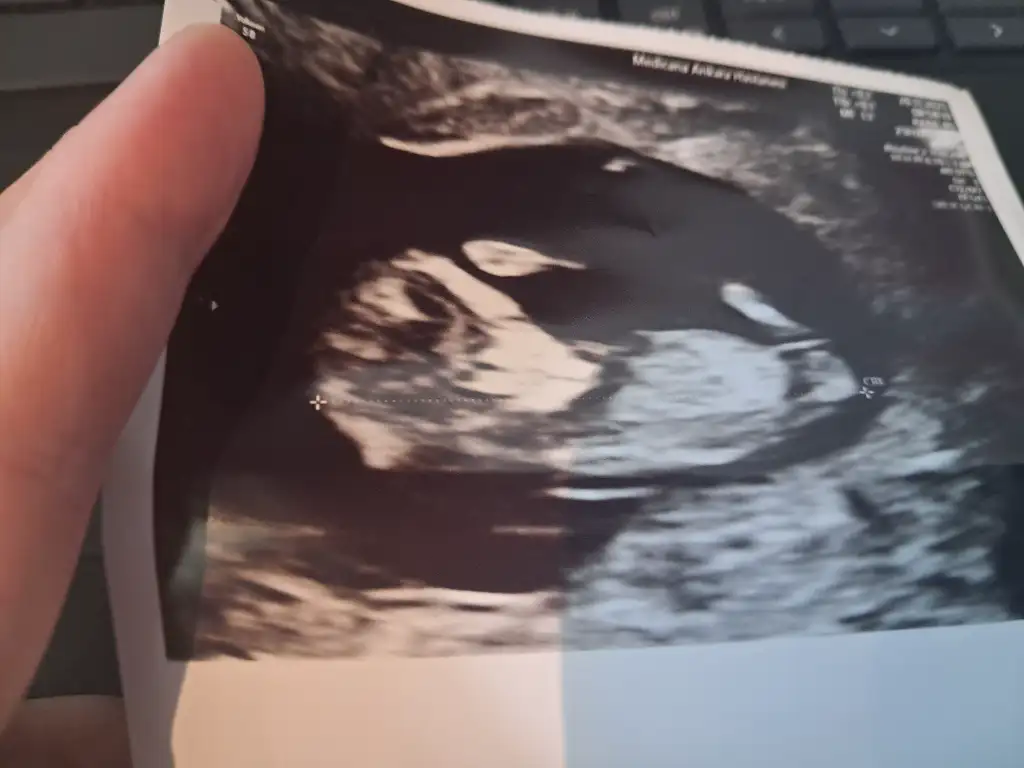

Tahminlerde hep kiz cikiyor cin takvimi rus takvimi gemni chat cpt birde sizin tahminleri alayım:)

Aslinda dr um gordu cinsiyeti ama emin olmaskfj icin söylemedi. :)